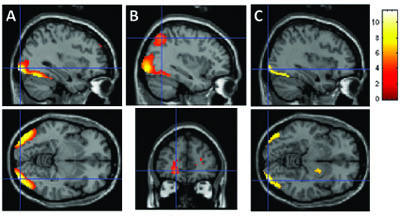

The contrast between object vs. non-object stimuli resulted in two clusters of significant brain activation (P < 0.001, FWE corrected). These included the posterior occipital regions (BA 18/19), the fusiform gyrus (BA 19/37), and the inferior temporal lobe (BA 20) bilaterally (Table 4 and Fig. 5). The contrast between colored objects vs. color non-objects (Table 4 and Fig. 5) resulted in additional activations in the right parahippocampal gyrus (BA 35/36), the inferior-superior parietal lobule (BA 7/39/40) bilaterally, and in the left inferior-middle temporal region (BA 20/21). In addition, frontal regions (P = 0.006, FWE corrected) were also significantly activated in colored objects vs. colored non-objects, including the left anterior-inferior frontal region (BA 10/47) and the left superior frontal region (BA 10). The contrast between B&W objects vs. B&W non-objects activated similar brain regions as observed in objects vs. non-objects, however the activation pattern was more restricted and primarily observed in posterior brain regions (right: P = 0.021, FWE corrected; left: P = 0.009, FWE corrected; Table 4 and Fig. 5).

A - Brain regions associated with objects compared to non-objects, B - Brain regions associated with color objects compared to color non-objects, C - Brain regions associated with B&W objects compared to B&W non-objects.